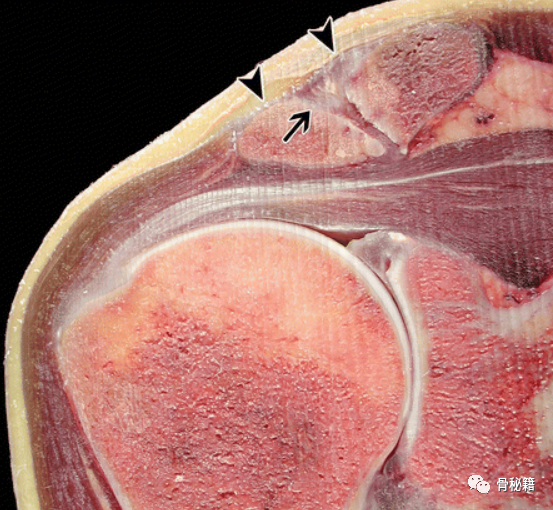

成人右肩的冠状病理切片照片显示 AC 关节的正常倾斜,通常从上外侧向前内侧倾斜